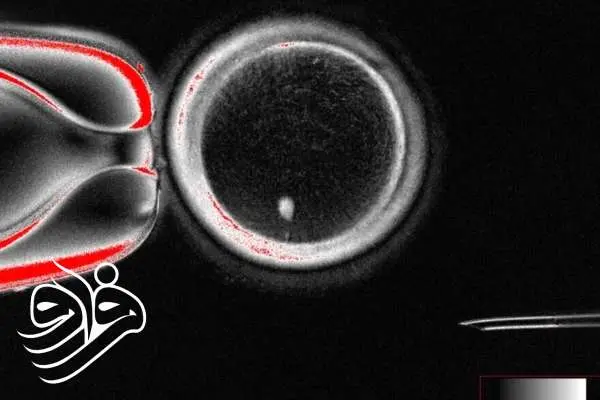

به گزارش خبرگزاری فارس، شوخرات میتالیوپ از دانشگاه اورگان و تیمش با استفاده از تکنیک انتقال هسته سلول سوماتیک (somatic cell nuclear transfer) سلولهای پوستی زنان را برداشتند و هسته آنها را به تخمک اهداکنندهای که هسته خود را از دست داده بود منتقل کردند. هسته سلول حاوی ۴۶ کروموزوم است که کد ژنتیکی انسان را تشکیل میدهد.چالش اصلی دانشمندان این بود که تخمک سالم انسان تنها ۲۳ کروموزوم دارد و برای تشکیل جنین، ۲۳ کروموزوم دیگر از اسپرم لازم است. با استفاده از ترکیبی به نام روسکوویتین (roscovitine)، تیم اورگان توانست نیمی از کروموزومهای اضافی را به یک ساختار موسوم به «بدن قطبی» منتقل کند تا کروموزومهای باقیمانده با اسپرم جفت شوند.

با این حال، در تخمکهای تولیدشده کروموزومها به صورت تصادفی جفت شدند و بسیاری از جنینها دارای تعداد یا ترکیب نادرست کروموزومها بودند. این بدان معناست که هنوز تخمکها برای ایجاد نوزاد سالم آماده نیستند و تیم تحقیقاتی در حال بهبود روش است.از ۸۲ تخمک تولیدشده، کمتر از ۱۰ درصد به مرحلهای رسیدند که معمولاً در IVF به رحم مادر منتقل میشوند و هیچکدام بیش از شش روز کشت نشدند.